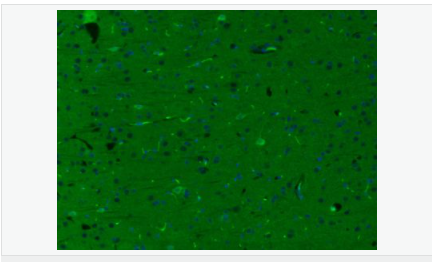

神經(jīng)膠質(zhì)生長因子